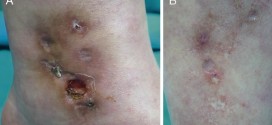

La arteritis de los miembros inferiores. Dureza y engrosamiento anormales de las paredes arteriales, resultado de inflamaciones, especialmente de la túnica íntima con tendencia a la obliteración del vaso. Enfermedad de los vasos arteriales de etiología diversa que provocan una obliteración o estrechez que obstruye el orificio de las arterias, disminuyendo el flujo sanguíneo arterial. Esta es una enfermedad que …